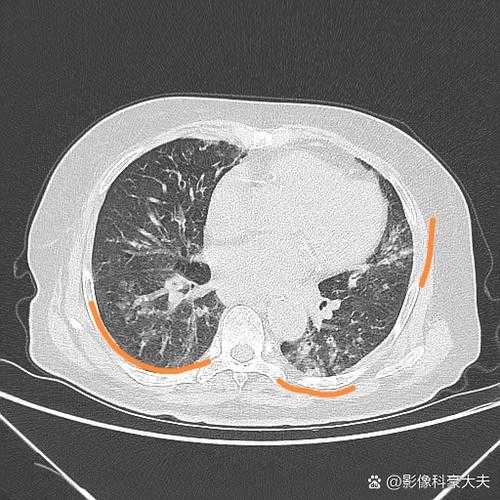

在2020-2022年新冠疫情期间,部分患者康复后出现咳痰困难等症状,引发对病毒复阳的担忧。吉林专家指出,咳痰困难可能由多种因素导致,包括病毒残留、呼吸道炎症或合并细菌感染,未必直接指向病毒复阳。复阳通常需结合核酸检测结果、临床症状及影像学变化综合判断。